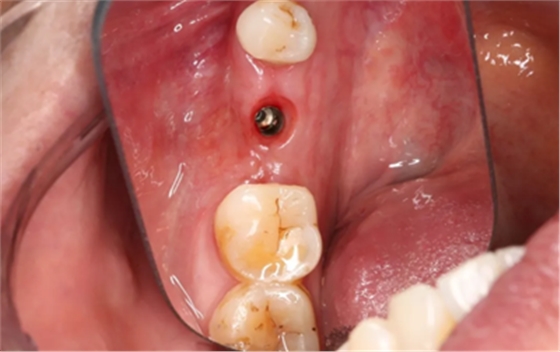

袖口形成,上皮健康,远中唇侧软硬组织欠丰满。

(摄于2018年5月25日)